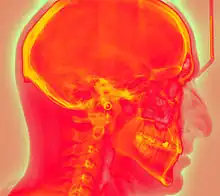

Projectional radiography using a photostimulable phosphor plate as an X-ray detector can be called "phosphor plate radiography"[1] or "computed radiography"[2] (not to be confused with computed tomography which uses computer processing to convert multiple projectional radiographies to a 3D image).

Computed radiography is used for both industrial radiography and medical projectional radiography. Image plate detectors have also been used in numerous crystallography studies.[5]

Medical X-ray Imaging

In phosphor plate radiography, the imaging plate is housed in a special cassette and placed under the body part or object to be examined and the x-ray exposure is made. The imaging plate is then run through a special laser scanner, or CR reader, that reads and converts the image to a digital radiograph. The digital image can then be viewed and enhanced using software that has functions very similar to other conventional digital image-processing software, such as contrast, brightness, filtration and zoom. CR imaging plates (IPs) can be retrofitted to existing exam rooms and used in multiple x-ray sites since IPs are processed through a CR reader (scanner) that can be shared between multiple exam rooms.[6]